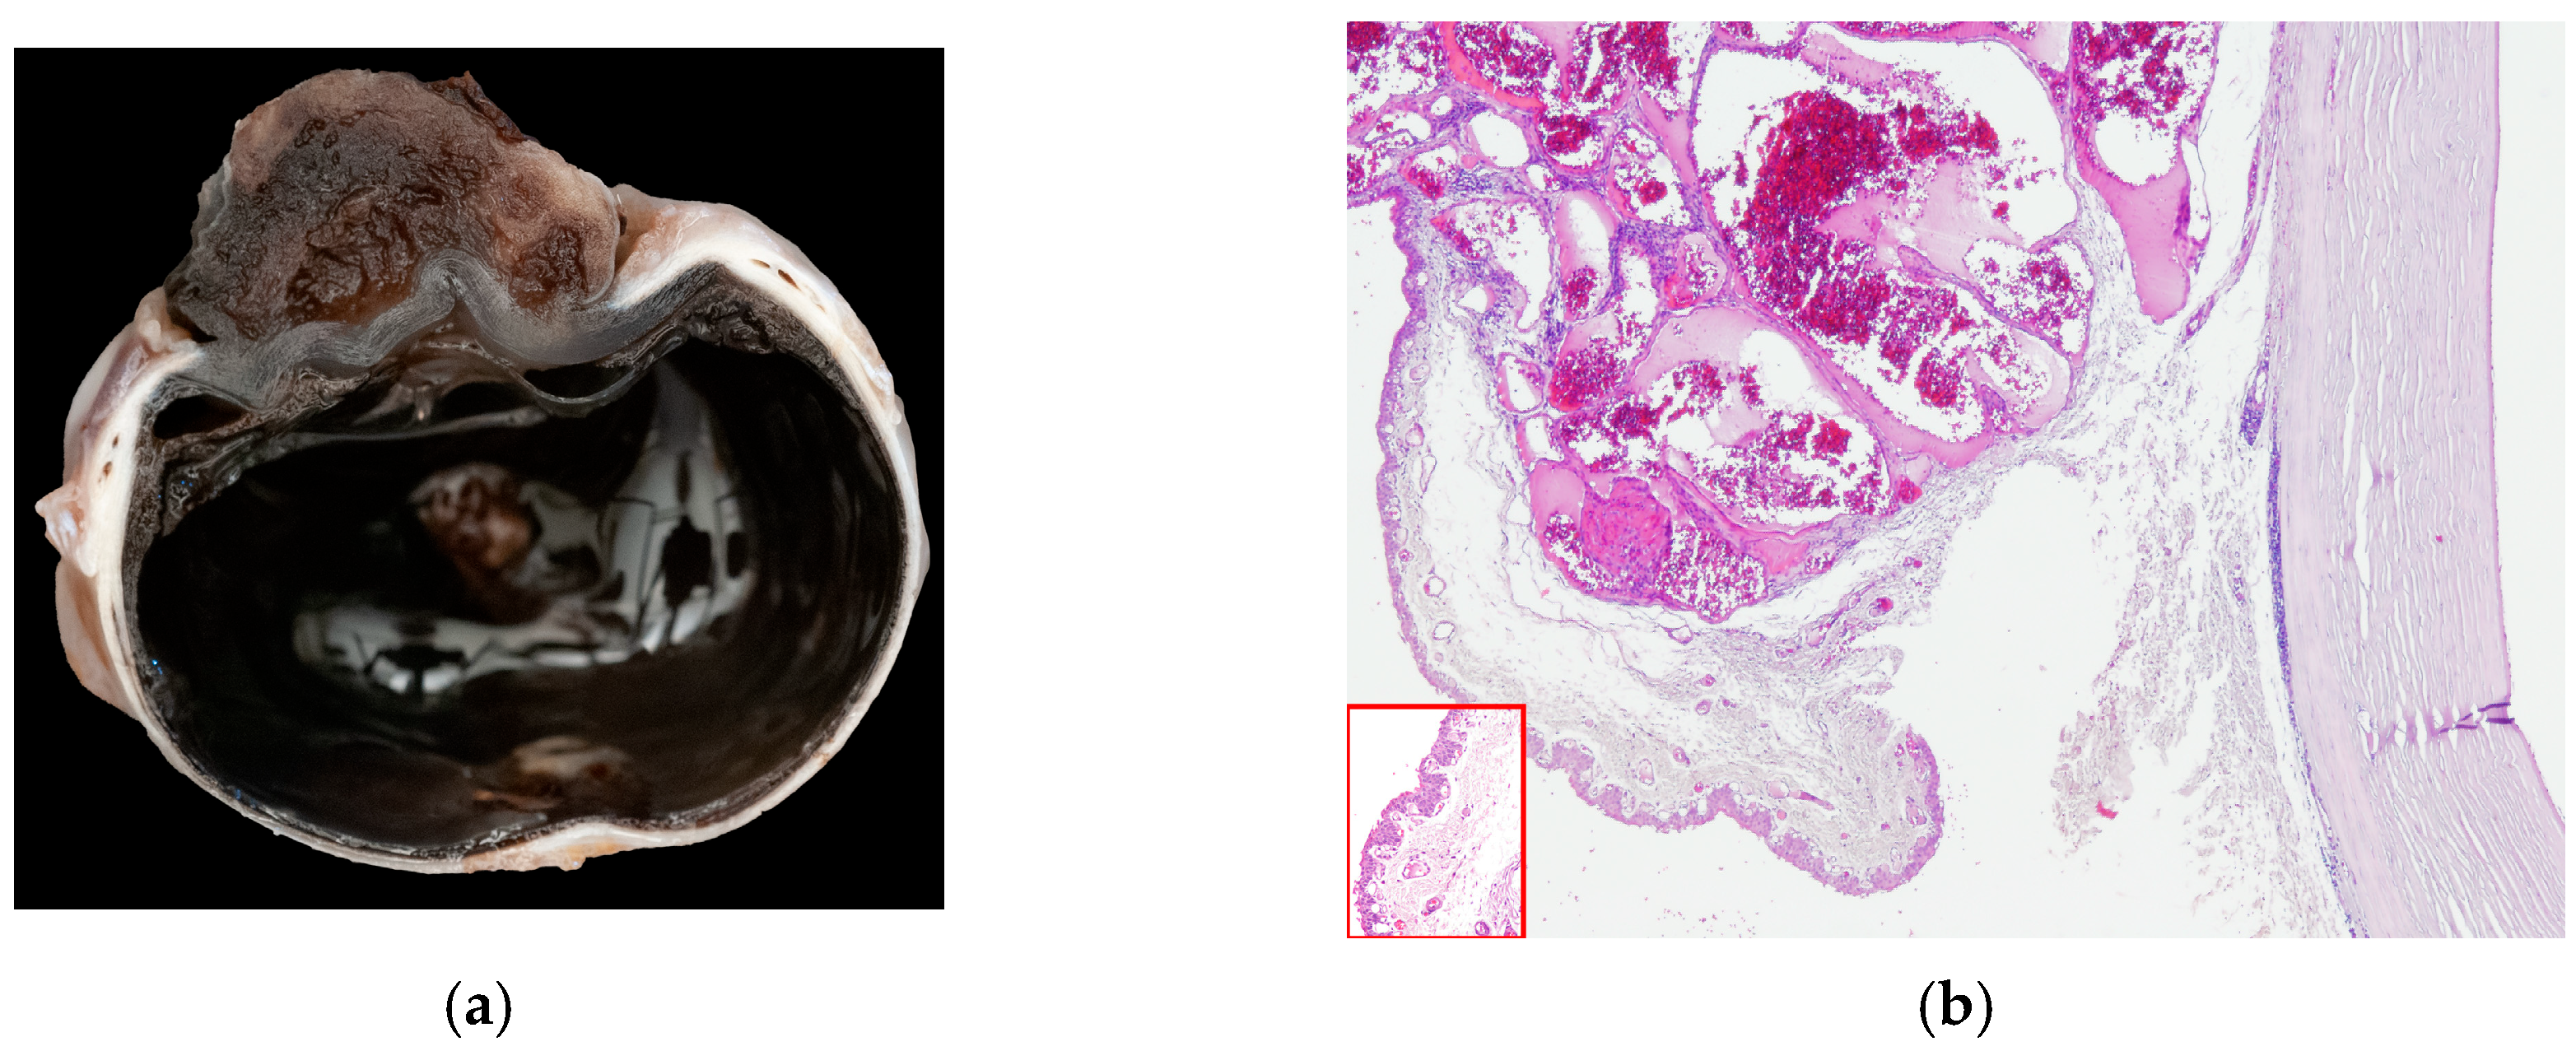

In 15 cats (15/104), a vascular corneal neoplasia was diagnosed: 8/15 were HAs and 7/15 were HSAs (Figure 3).

Figure 3.

(a) Cat, eye globe, a large vascular neoplasm grows onto the corneal surface; (b) cat, eye globe: corneal hemangioma and symblepharon; conjunctival tissue relies on corneal stroma, substituting corneal epithelium, with tumor expanding its lamina propria (EE, 4×). Inset: Detail of the conjunctival epithelium and stroma that substitutes superficial corneal layers (EE, 40×).

The mean age of affected cats was 9.6 years, ranging from 3 to 14 years. Males were more represented (10/15; 67%; three intact and seven neutered) than females (5/15; 33%; two intact and three neutered). All cats were European Domestic Short Haired.

There was a history of symblepharon and/or FHV1 infection in 6/15 cases, traumatic injuries such as corneal ulcer or perforation in 2/15 cases, and 1/15 congenital palpebral malformation. The clinical history was not available in 6/15 cases.

Fourteen (14/15) neoplasia grew onto the cornea; in one single case (1/15), there was limbal extension. Inflammation was mild or absent in most cases (10/14) and moderate in the others (4/14). In one single case, stromal elastosis was observed (case 14, Table A4, Appendix A).